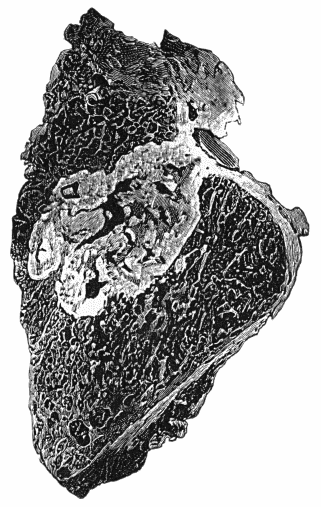

162.Bones of Knee in Charcot's Disease 533

163.Charcot's Disease of Left Knee 534